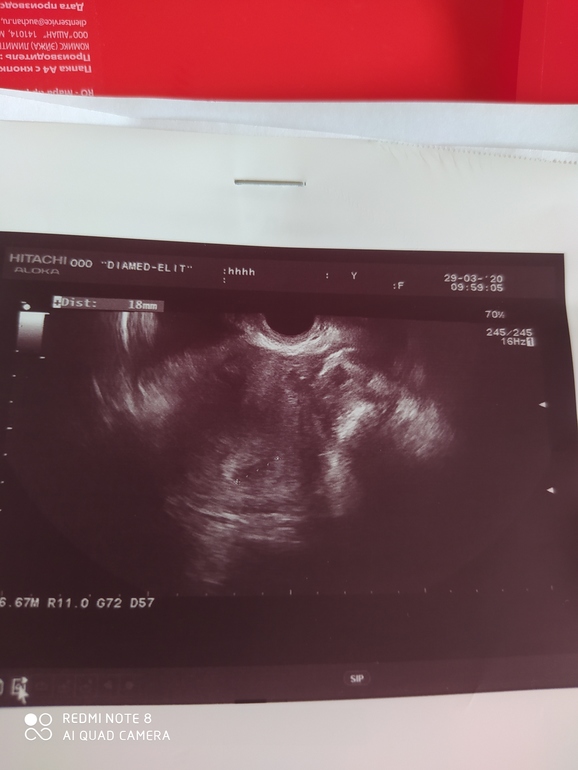

Да тоже ПЯ какое-то гигантское, 32мм. Сказала ещё про пятно какое-то темное...типа это прошлая ЗБ. Хотя у меня была бхб и вряд ли там вообще что-то могло быть с таким маленьким хгч. ЧСС правда до 115 уд/мин, хотя уже вроде поболее должно быть. Но ладно, главное, что бьется) я просто сравниваю замеры даже яичников с прошлым узи, так они разнятся. Через неделю к своему Ре, посмотрим, что он мне скажет) Главное, чтоб пасли малышонки.

Да в Инвитро пошла к своей старой гинекологичке, у которой наблюдалась ещё до ЭКО) Вроде человек с опытом, но узи наверное не ее конёк)) по ее измерениям получается больше 1 мм в день. Мне по узи в среду ставили тоже срок меньше на 6 дней, чем по акушерскому. Сегодня вот якобы почти догнал. 🤷♀️ Через недельку к Ре, посмотрим что скажет)